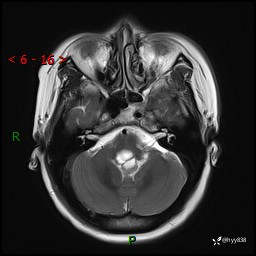

性别:女

年龄:47岁

简要病史:头晕1年余,间断恶心不伴呕吐

颅脑MRI平扫+DWI

轴内、轴外占位

轴内或轴外肿瘤